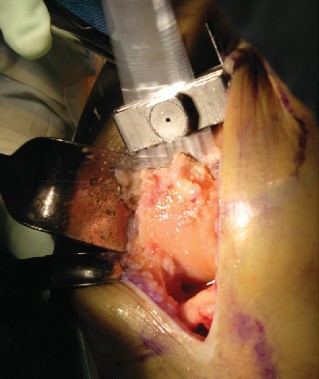

الخطوة 2: قطع عظم الفخذ (Femoral Cuts)

- الدليل داخل النخاع (Intramedullary Guide): يُستخدم دليل داخل النخاع لعظم الفخذ لضمان دقة القطع.

- ثقب كبير: يُحدث ثقب كبير في الجزء الأوسط من الشق بين اللقمتين.

- تحديد الزاوية: يُضبط الدليل داخل النخاع بزاوية 4 درجات ويُدخل في قناة الفخذ. يتم تركيب قالب القطع الفخذي البعيد (distal femoral cutting block) على الدليل.

- التثبيت والقطع: يُثبت القالب في مكانه ويُقطع الجزء البعيد من عظم الفخذ.

اعتبارات هامة (Pitfalls):

- موضع فتحة البدء في عظم الفخذ قد يؤثر على زاوية الانحراف (valgus angle). يساعد التخطيط المسبق لقناة النخاع وزاوية الانحراف على ضمان المحاذاة الصحيحة.

أدوات خاصة: يستخدم الأستاذ الدكتور محمد هطيف أدوات جراحية دقيقة وتقنيات متطورة تتيح رؤية ممتازة لكل عملية قطع، مما يضمن الدقة والأمان. كما يستخدم مبعدات جراحية متخصصة (retractors) مصممة لجراحات استبدال مفصل الركبة طفيفة التوغل.

- يجب أن تكون كمية العظم المُزالة مساوية لسُمك البدلة الاصطناعية لضمان التطابق المثالي.

مفاتيح النجاح الجراحي (Pearls):

- الشد المناسب للمبعدات الجراحية يمنع تمزقات الجلد أو إصابات الأربطة أو العظام.

- يمكن تعديل شد المبعدات لكشف منطقة معينة من الركبة ثم المنطقة التالية حسب الحاجة.

- يجب وضع دليل قطع عظم الساق (tibial resection guide) أقصى ما يمكن جانبيًا دون إلحاق الضرر بالجلد أو وتر الرضفة.